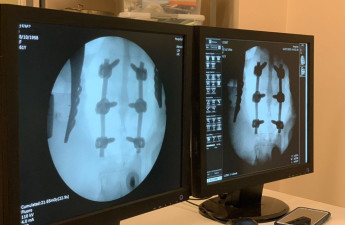

На Волині лікарі оперували хребет жінці, яка впала з висоти

У Ковелі жінці, яка впала з висоти, провели складну операцію на хребті